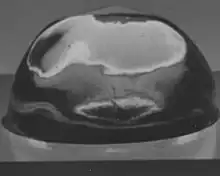

The capsule helps give the lens its more spherical shape in aquatic vertebrates such as fish and more ellipsoidal shape in land based vertebrates such as sheep. In humans the lens ellipsoid becomes more flattened with age.[15] The capsule is the basement membrane for the epithelial cells at the front of the lens and the rapidly growing more flexible fiber cells of the back of the lens and below the epithelium at the front. Without the capsule substrate forming a tense support these cells lose their form as in the picture of a decapsulated sheep lens.